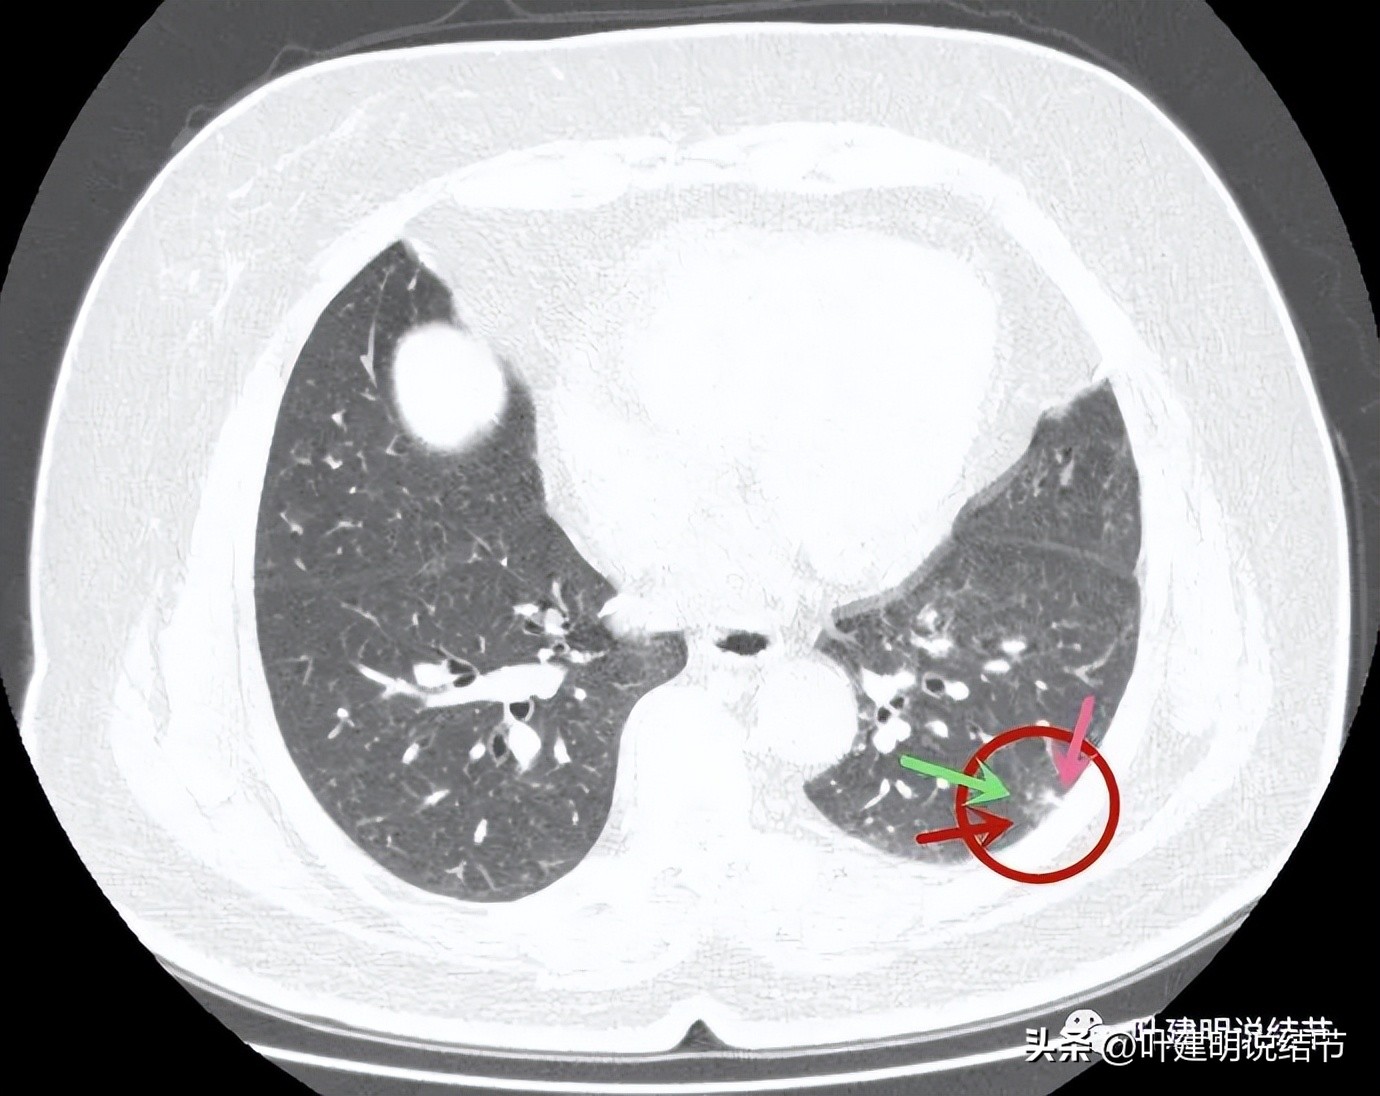

病灶4:左下叶实性结节,即主病灶,实性不是很致密的病灶,胸膜下,边界较清,邻近胸膜没有牵拉。有恶性可能性(良性的用什么疾病能解释?好像错构瘤、硬化性血管瘤、结核、肉芽肿性炎、淋巴结、急性炎症、隐球菌等常见的都靠不太上)。

病灶4:见有血管进入病灶,整体上是偏实性的,但感觉不太致密

病灶出现,磨玻璃部分密度过低,边缘有实性成分,贴着胸膜

病灶近肺门侧有斑片状磨玻璃影(绿色箭头),病灶与胸壁间贴着,但没有牵拉(蓝色箭头),大部分是实性密度(粉色箭头)。